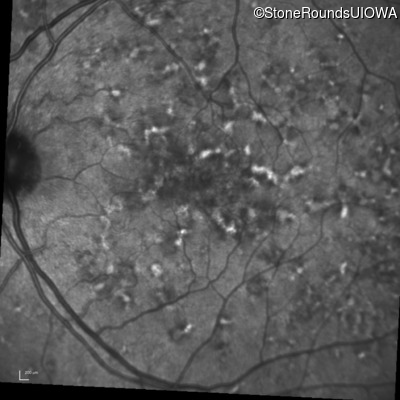

Blue Autofluorescence - Right - 20/20 -1 sc

Exemplar